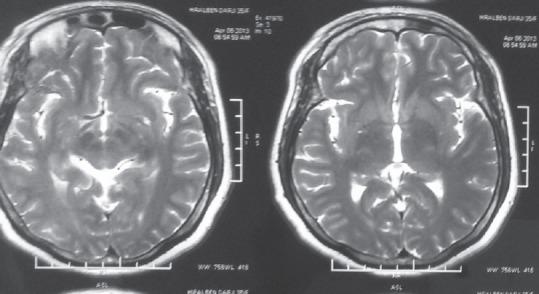

Isolated sellar tuberculoma is a very rare condition and usually presents with headache and decreased vision. It can present with panhypopituitarism with 3 nerve palsy. Tuberculoma mimics pituitary adenoma clinically as well as radiologically and requires endoscopic transsphenoidal surgery and histopathological examination for the final diagnosis. We present a rare case of a 40-year-old female presented with headache, decreased vision, and unilateral 3 nerve palsy with panhypopituitarism.

孤立性鞍区结核瘤是一种非常罕见的病症,通常表现为头痛和视力下降。它可伴有全垂体功能减退及动眼神经麻痹。结核瘤在临床和影像学上都酷似垂体腺瘤,最终诊断需要经鼻蝶窦内镜手术及组织病理学检查。我们报告一例罕见病例,一名40岁女性,表现为头痛、视力下降、单侧动眼神经麻痹伴全垂体功能减退。